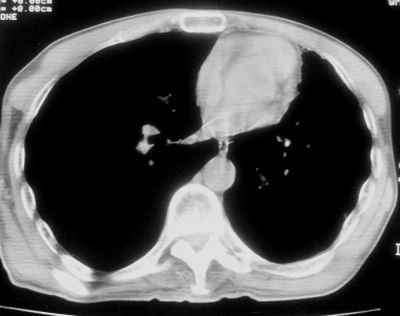

标题: CT11864:男,47岁,反复咳嗽、咯痰、咯血3年,请分析. [打印本页]

患者,男,47岁,反复咳嗽、咯痰、咯血3年,再发5天。痰培养未找到真菌、抗酸杆菌、癌细胞。

左肺上叶体积明显缩小,其内见多发透光区,纵隔向左侧移位,左肺下叶多发班片状病灶,边界模糊,1左肺上叶先天肺发育不全,2左肺下叶肺炎,

左肺上叶结核伴肺纤维化,纵隔移位,左肺下叶感染性病变,建议抗炎抗结核后复查,双肺气肿.

以下是引用xulianj在2008-2-25 21:01:00的发言:[br]左肺上叶结核伴肺纤维化有霉菌球形成,纵隔移位,左肺下叶感染性病变,建议抗炎抗结核后复查,双肺气肿.

考虑:左肺慢纤伴霉菌球形成、双肺全小叶型肺气肿。

1)考虑为:左肺上叶肺结核(空洞形成),伴左下肺感染;不排除霉菌感染可能。2)肺气肿。

左肺上叶结核伴肺纤维化空洞形成并左肺下叶感染,纵隔牵拉移位,建议作进一步检查排除左侧肺霉菌感染可能。